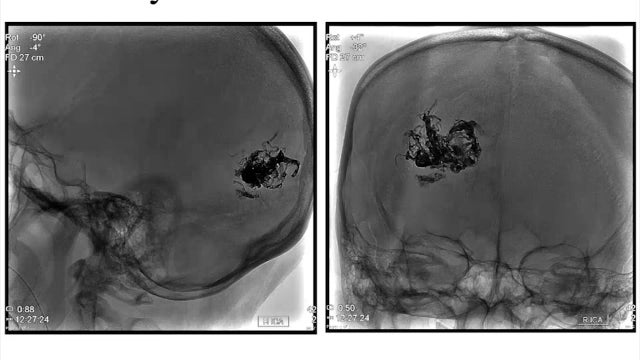

Doctors diagnosed what's called an arteriovenous malformation, or AVM -- an abnormal tangle of blood vessels that disrupts blood flow the brain. One of Chan's grandmothers had died of the same thing.

First, they flooded the AVM with medical glue to stop the blood flow. Then they delicately removed the tangle from inside her brain.